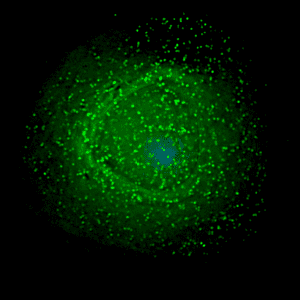

PrEP is for people who do not have HIV but are at a very high risk of contracting the disease. This drug is highly effective in preventing HIV, reducing the chance of contracting it through sex by about 99% when taken once a day.

Even if someone is exposed to HIV, taking PrEP can work to keep the virus from establishing a permanent infection.